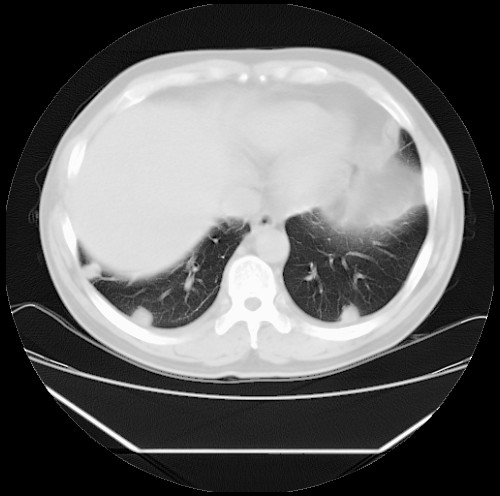

标题: CT22085:双肺多发结节

男,44岁,咳嗽,痰中带血2天。

病灶大部分位于胸膜下,结节大小相差不是很大,肺尖太干净。这种结核没见过,我认为可排除。

首先考虑转移,不除外肉芽肿、真菌感染。建议查其它。

除肺内及胸膜下可见多发大结节外,在肺小叶中心核、小叶间隔及支气管血管束上亦可见多方小结节,可以认为是随机分布。考虑转移可能性大。

仔细观察病灶形态,病灶边界部分清楚,结合临床症状,首先考虑转移,纵隔内多个肿大淋巴结影。

双肺血管纹理末端多发类圆形结节,边界光滑清晰 气管前腔静脉后淋巴结肿大

考虑转移瘤

沿血管分布,位于血管末端。转移瘤多见,血行性菌栓也可见到。

本例双肺多发类圆形高密度灶,边清,结合病史多考虑双肺多发转移改变,可以结合实验室检查。